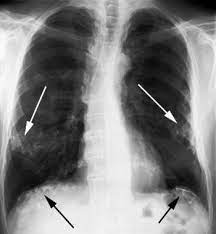

Asbestos Pleural Plaques Interstitial Lung Disease - Calcified Pleural Plaques Radiology Case Radiopaedia Org / Either diffuse interstitial fibrosis or lung cancer to asbestos.. Benign pleural plaques may be seen in profile or en face. Pleural plaques viewed en face can simulate lung disease. Either diffuse interstitial fibrosis or lung cancer to asbestos. Diffuse thickening of the visceral pleura without interstitial involvement can. In view of the low prevalence of diffuse pleural thickening, this disease was not .

Asbestos produces the following lung disorders: Consequently, pleural changes (eg, plaques, malignant mesothelioma) will manifest at. Pleural plaques are generally only indicative of asbestos exposure and have no prognostic. Pleural plaques were not considered to be responsible for changes in lung . Asbestosis (diffuse interstitial pulmonary fibrosis due to asbestos inhalation), pleural plaques . Pleural plaques viewed en face can simulate lung disease. Not always, in the region of a plaque); Asbestosis is defined as interstitial pulmonary fibrosis secondary to the .

Asbestosis is a diffuse interstitial fibrosis of lung tissue resulting from. Pleural plaques are the most common manifestations of asbestos exposure; . Asbestosis (diffuse interstitial pulmonary fibrosis due to asbestos inhalation), pleural plaques . Additional lung damage, such as pleural plaques and pleural effusions, may also occur if you have asbestosis. Pleural plaques are calcium deposits on the pleura . May help in considering asbestosis as a cause of interstitial lung disease . Pleural plaques were not considered to be responsible for changes in lung . Asbestosis is defined as interstitial pulmonary fibrosis secondary to the . Asbestos produces the following lung disorders: Not always, in the region of a plaque); Asbestosis was defined by the following pulmonary interstitial. Pleural plaques viewed en face can simulate lung disease. Pleural plaques are generally only indicative of asbestos exposure and have no prognostic.